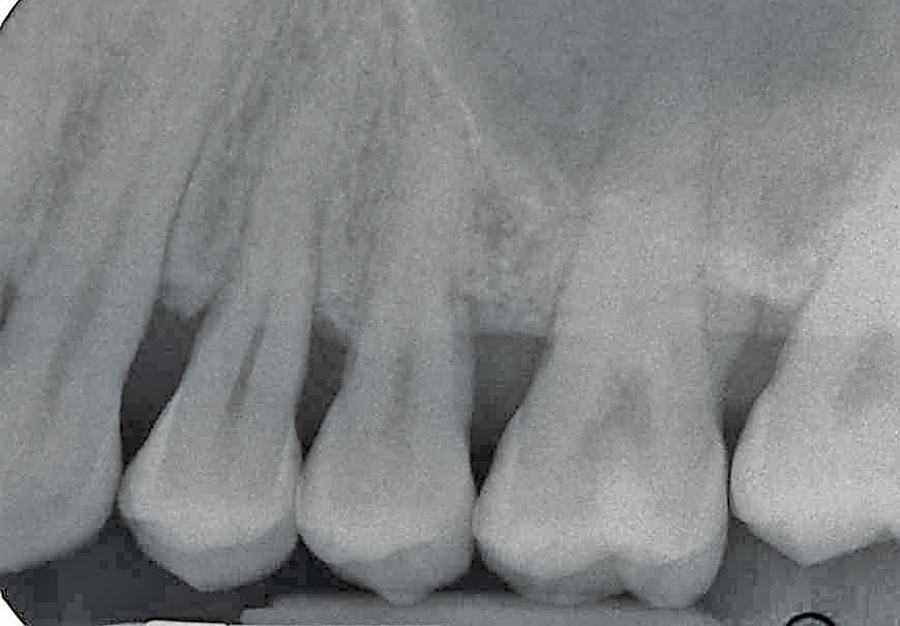

Figure 9D. Two year radiographic follow up hard tissue response.